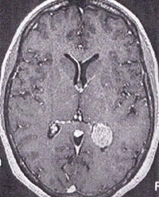

What neoplasm is depicted on the following contrasted T1-weighted MRI in an asymptomatic adult male?